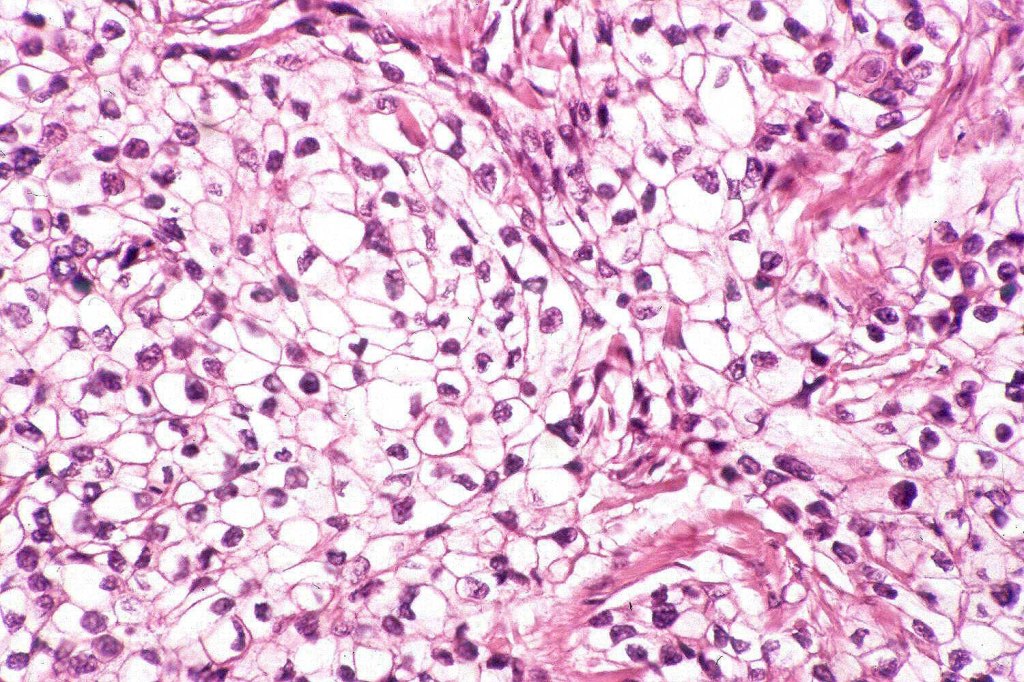

Histological features

•Clear cell change results from cytoplasmic glycogen accumulation

•Can be focal or involve most of the tumor